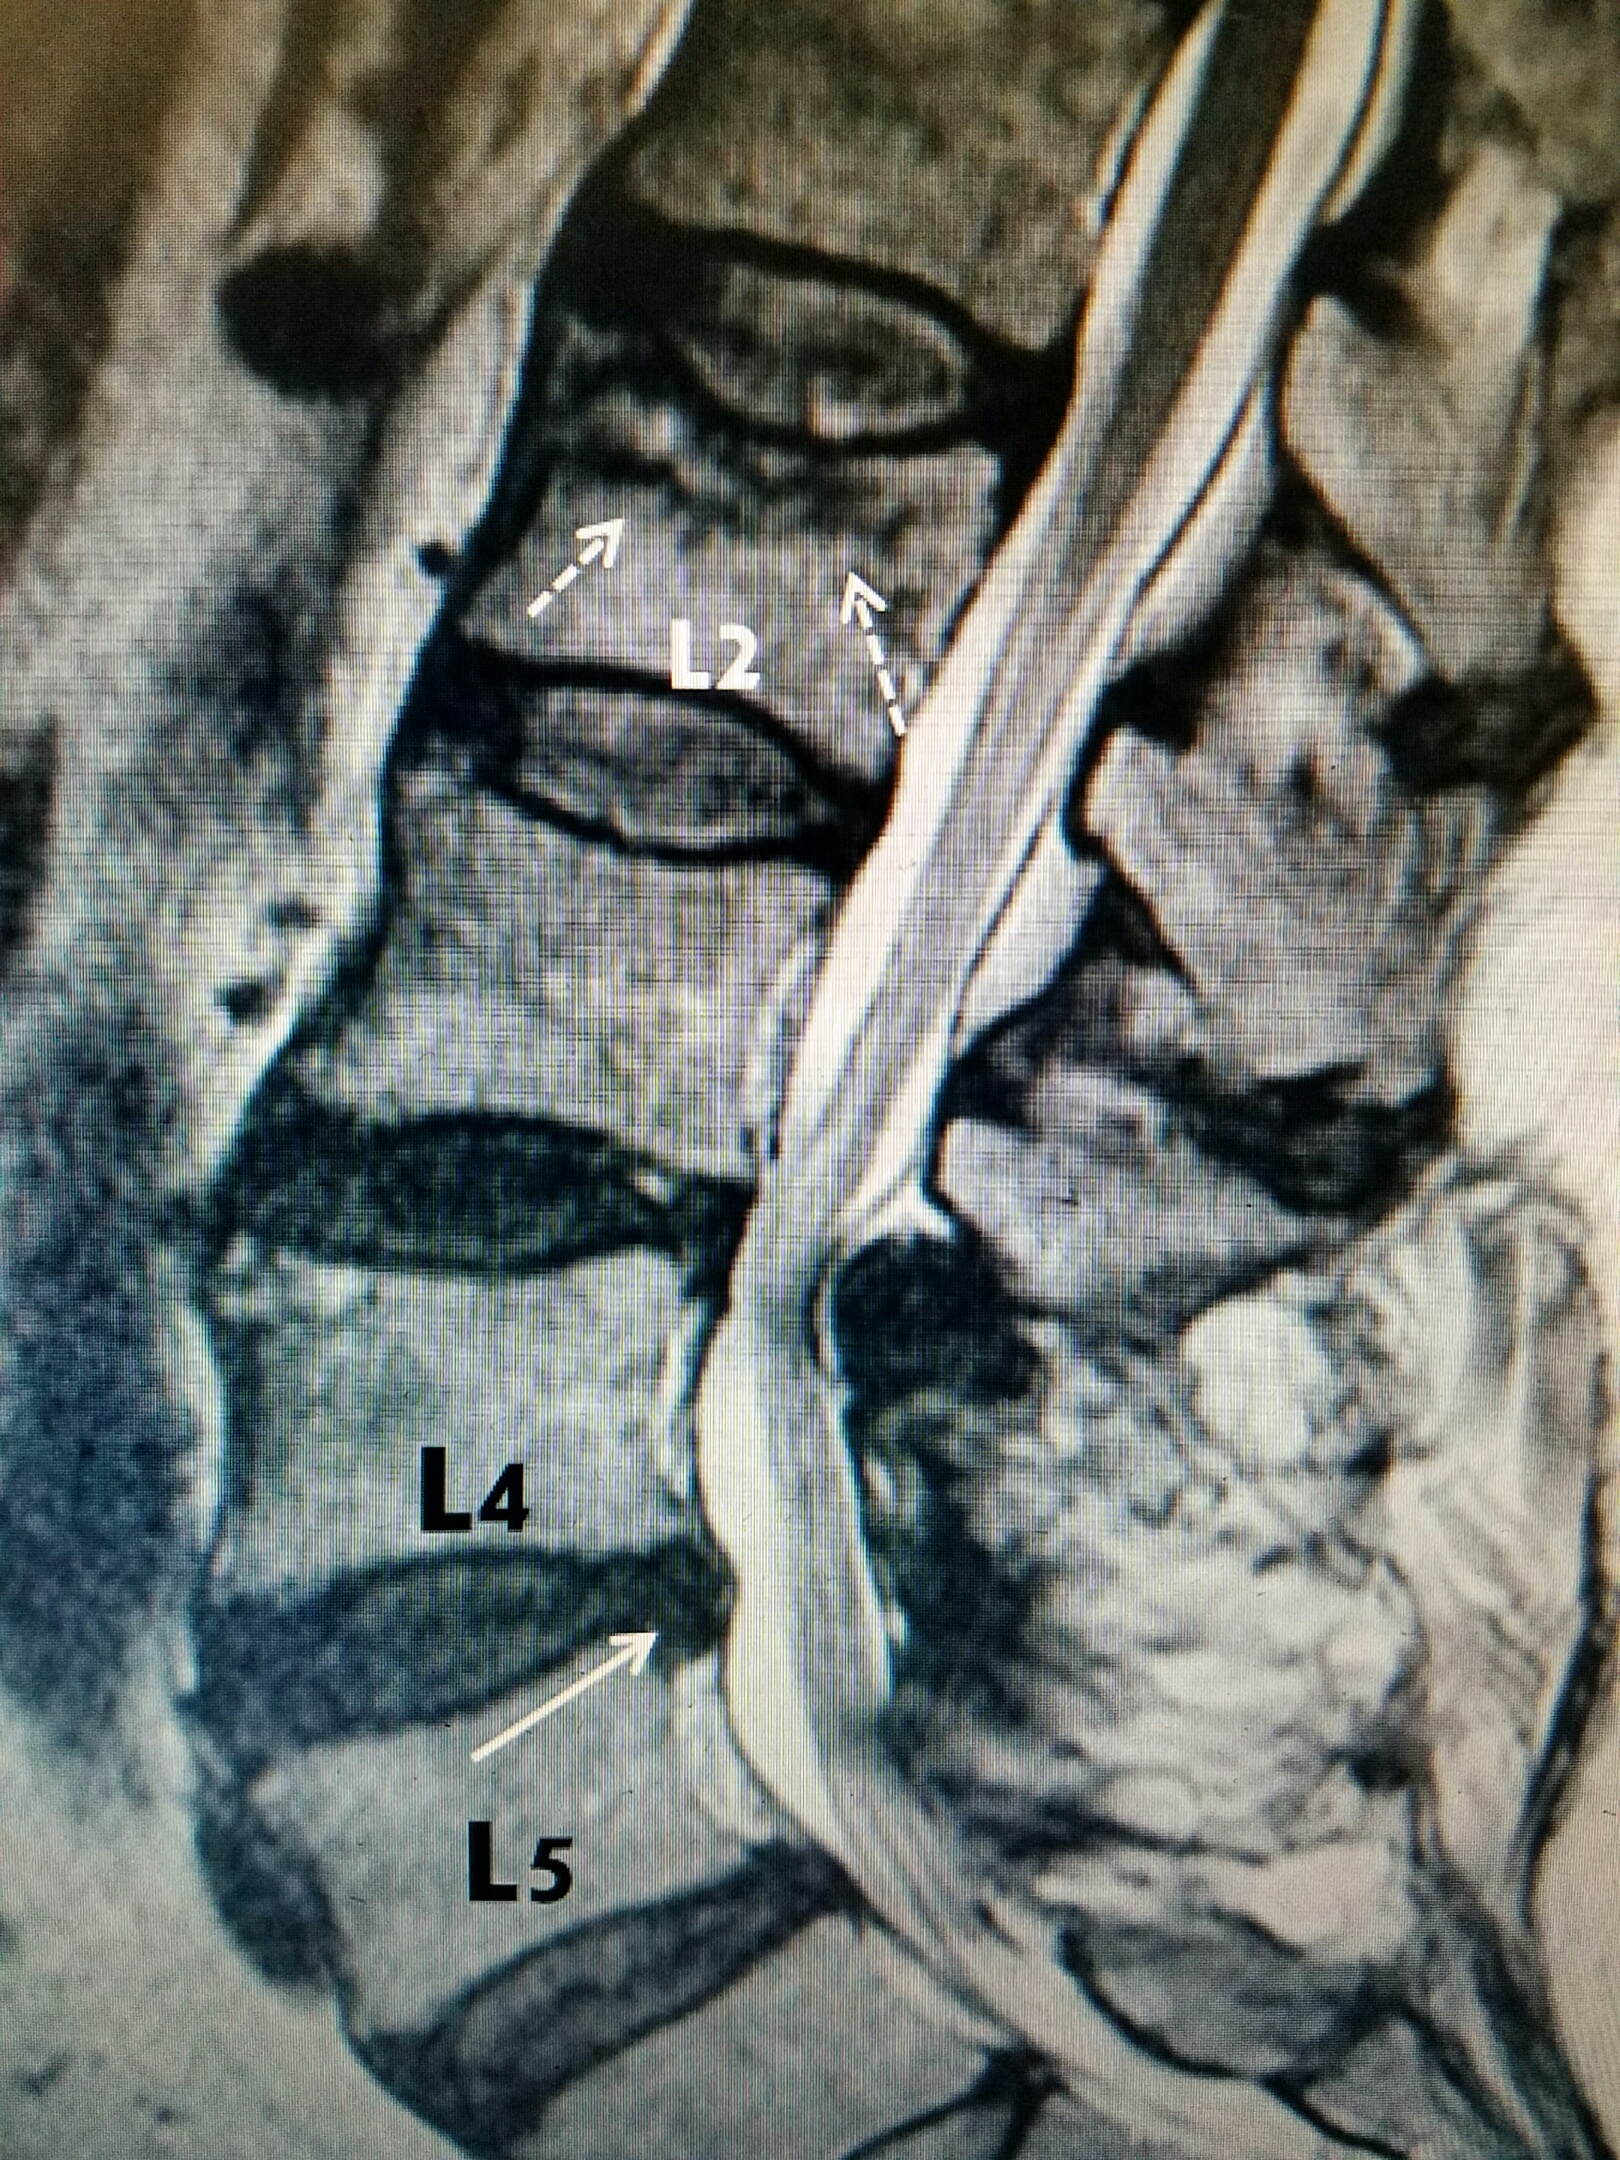

Lumbosacral spine, lateral view. Depression of the superior endplate of

Lumbar spine MRI sagittal view of a patient with lower back pain. A T11 Lumbar Superior Endplate caudal endplate of a typical lumbar vertebra, which consists of a ring apophysis (black arrow ) and central osseous endplate (red asterisk). midline back pain is the hallmark symptom of lumbar compression fractures. the superior vertebral end plate lies on the inferior surface of the vertebral body, which sits superiorly in the intervertebral joint. eight‐five rectangular. Lumbar Superior Endplate.

Lumbosacral spine, lateral view. Depression of the superior endplate of Lumbar Superior Endplate caudal endplate of a typical lumbar vertebra, which consists of a ring apophysis (black arrow ) and central osseous endplate (red asterisk). the vertebral endplates are critical for maintaining disc function yet like other components of the disc are. midline back pain is the hallmark symptom of lumbar compression fractures. eight‐five rectangular specimens were dissected from. Lumbar Superior Endplate.